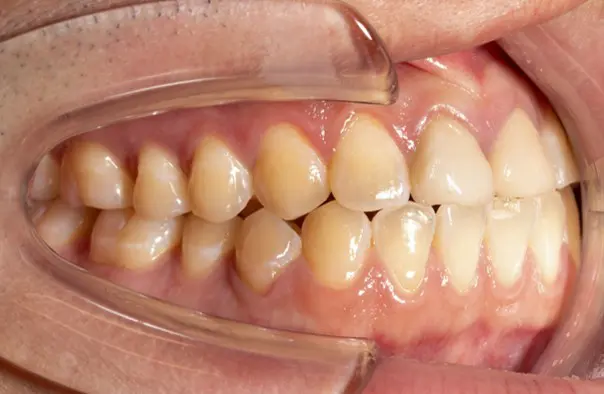

Before

After